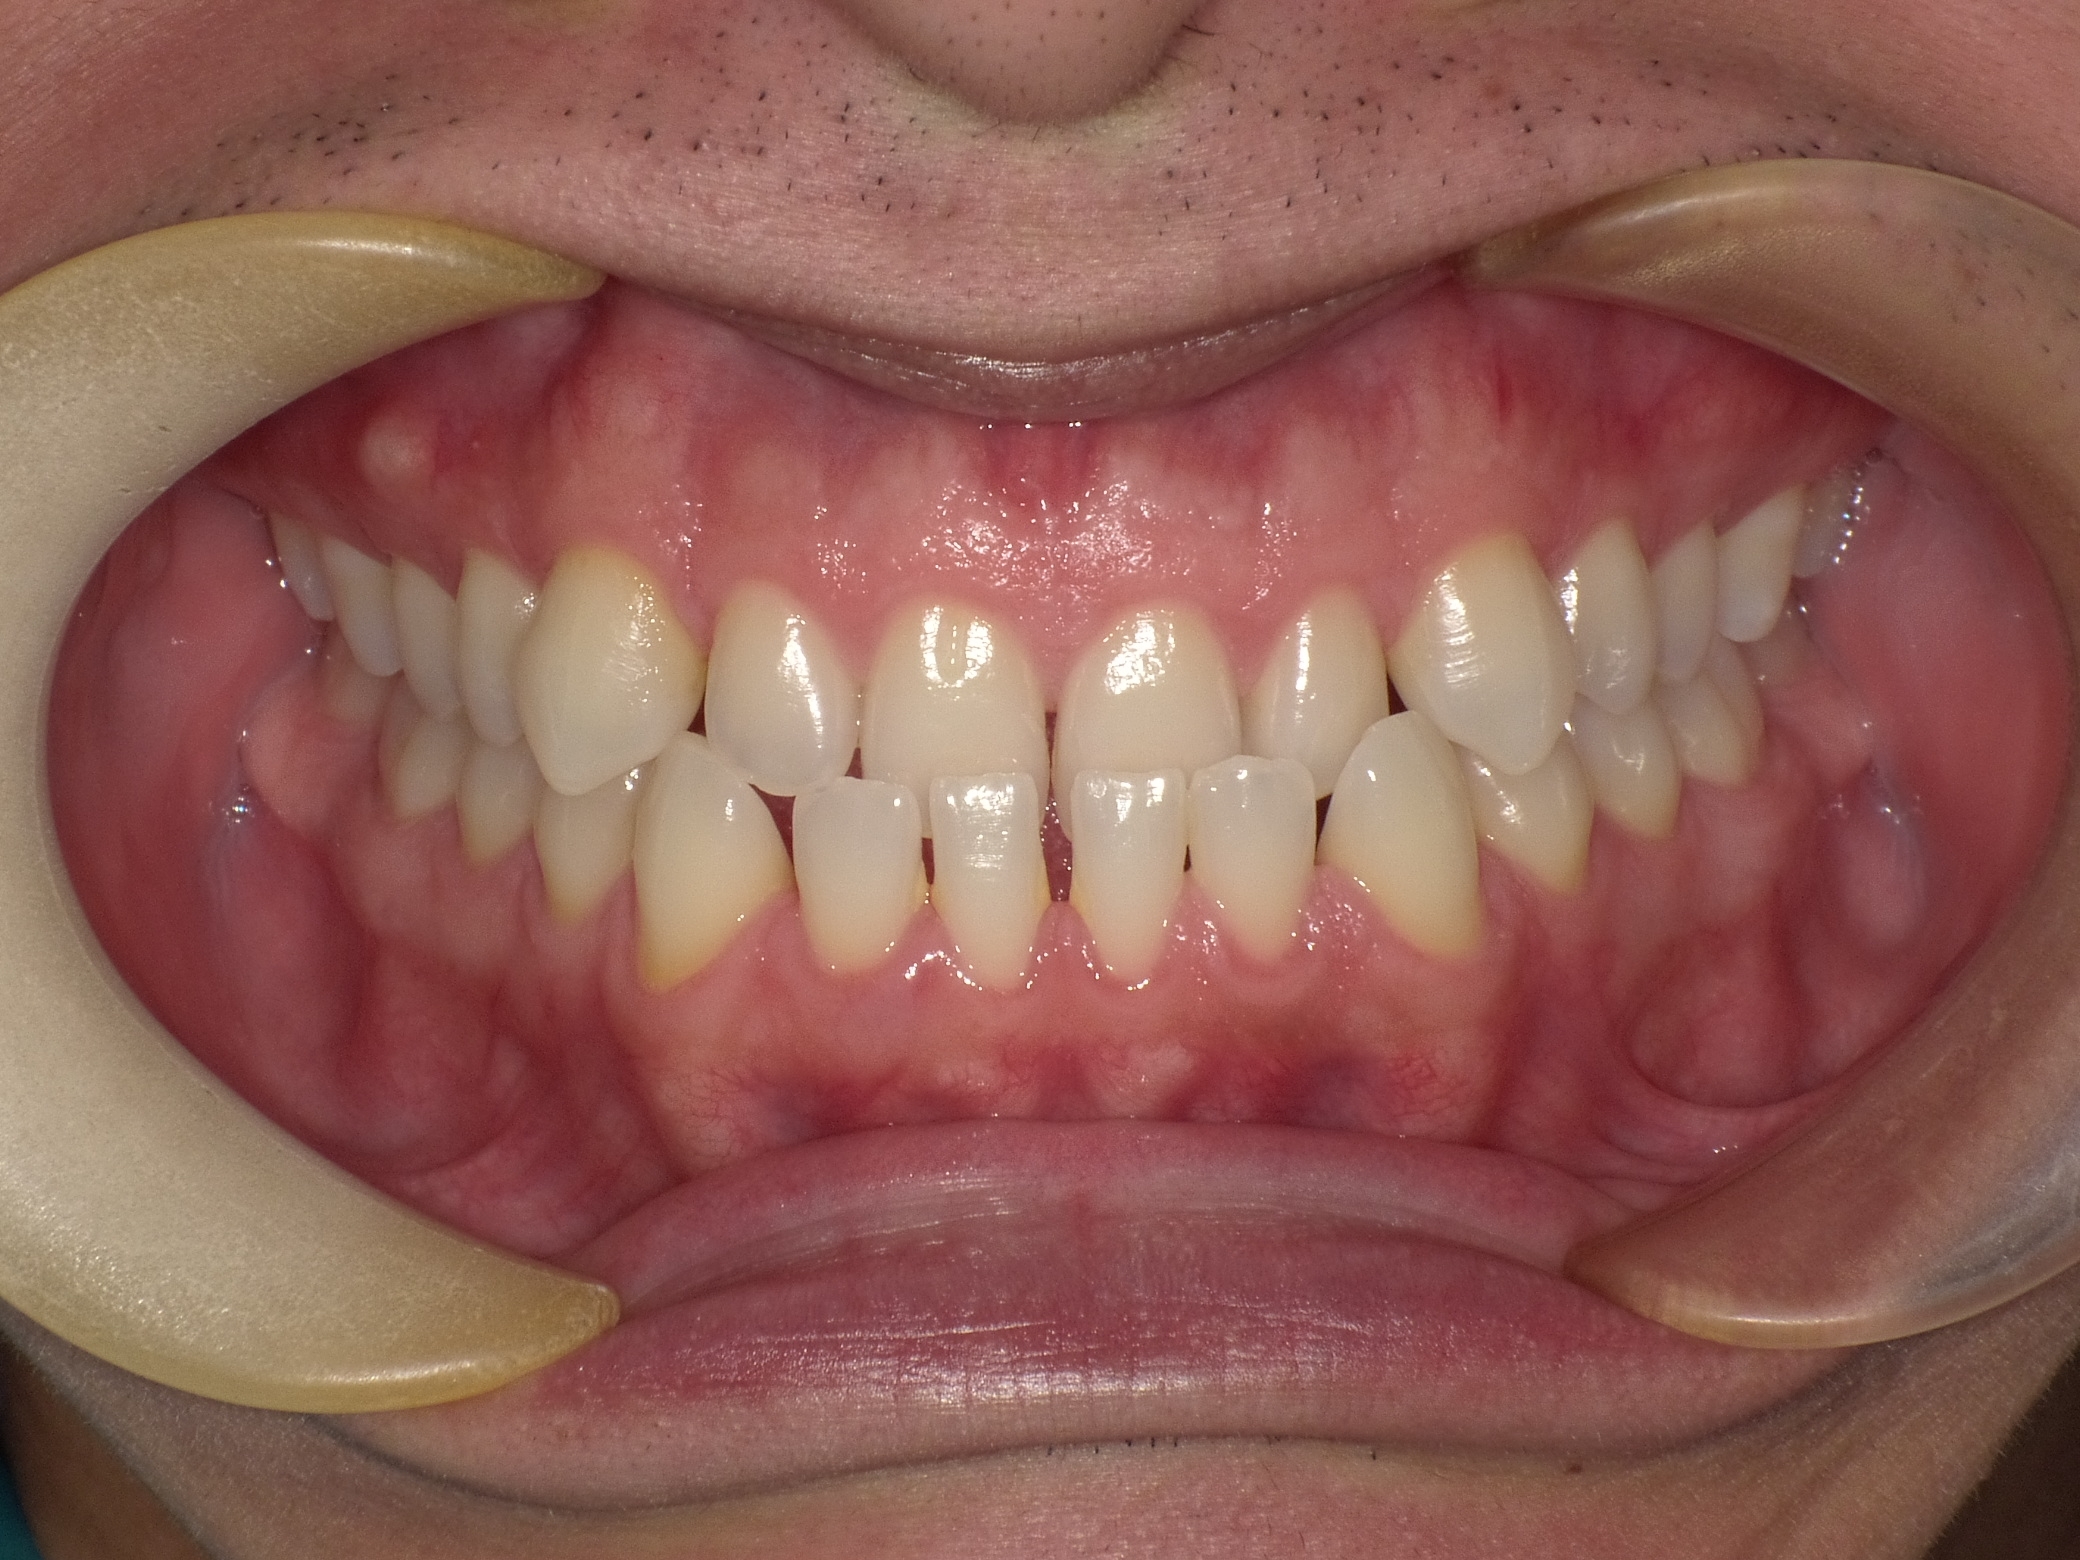

受け口とは、下の前歯が上の前歯より前に出ている噛み合わせのことを指します。専門的には「反対咬合」や「下顎前突」と呼ばれます。

特に骨格性の受け口は成長の影響を受けやすいため、治療開始のタイミングが非常に重要です。